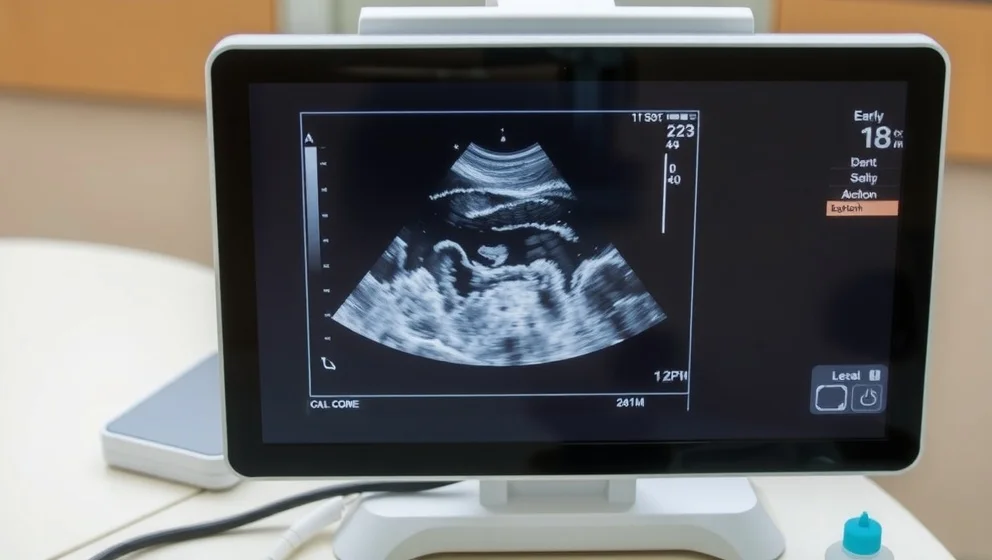

Vid vecka 6 8 syns hjärtslaget, ofta som en liten fladdrande rörelse på skärmen. Fostret mäts och barnmorskan räknar hur många foster det finns. Många par blir djupt rörd när de hör ordet "hjärtslag" för första gången.

Vecka 18 20 ger en detaljerad anatomisk granskning. Här kan man ofta se barnets kön om det ligger rätt. Ultraljudsteknikern kontrollerar att alla organ utvecklas normalt och att allt ser bra ut.

Tidiga ultraljud görs ofta vaginalt före vecka 8, eftersom det ger bättre bildkvalité. Senare undersökningar sker på magen istället.